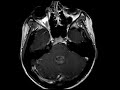

Ependymoma

This case shows a multilobulated T1 isointense, T2 FLAIR hyperintense heterogeneously enhancing mass centered in the fourth ventricle which extends through the foramina of Magendie and Luschka as well as through the foramen magnum. The differential diagnosis for a posterior fossa mass in a young patient includes juvenile pilocytic astrocytoma, medulloblastoma, and ependymoma. The imaging features in this case of a “soft” heterogeneous fourth ventricular tumor which squeezes through the foramina are characteristic of an ependymoma which was subsequently proven on pathology. The B-subtype which presents in older children and adults has a better prognosis than the A-subtype which presents most commonly in infants. Incidentally noted is what appears to be a small pars intermedia cyst of the pituitary on the sagittal post contrast images.